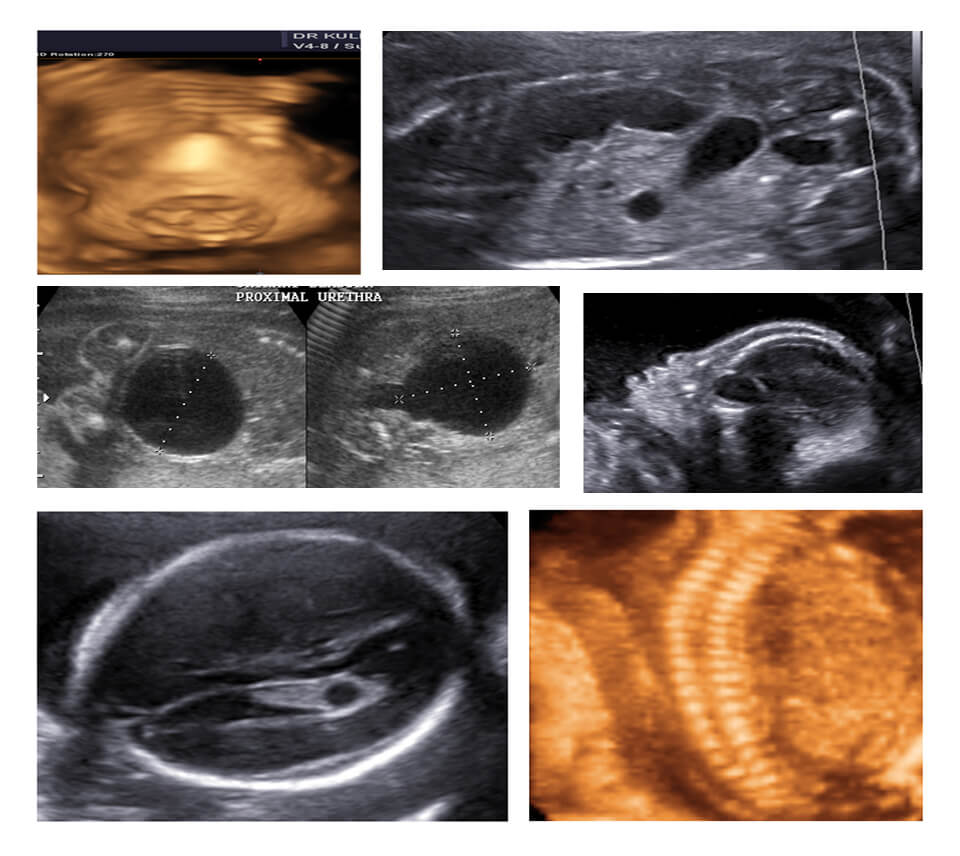

MODULE 4 :- EARLY PREGNANCY

04-10 WEEKS : EVALUATION OF EARLY NORMAL PREGNANCY, 04-10 WEEKS : ABNORMAL LOCATION / DEVELOPMENT/ PROGRESS, 10-14 WEEKS: SCREENING STRATEGIES AND WORKUP, 10-14 WEEKS: FETAL ANATOMY n STRUCTURAL DEFECTS (EYE OPENER